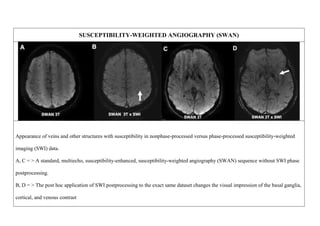

SUSCEPTIBILITY-WEIGHTED ANGIOGRAPHY (SWAN)

Appearance of veins and other structures with susceptibility in nonphase-processed versus phase-processed susceptibility-weighted

imaging (SWI) data.

A, C = > A standard, multiecho, susceptibility-enhanced, susceptibility-weighted angiography (SWAN) sequence without SWI phase

postprocessing.

B, D = > The post hoc application of SWI postprocessing to the exact same dataset changes the visual impression of the basal ganglia,

cortical, and venous contrast